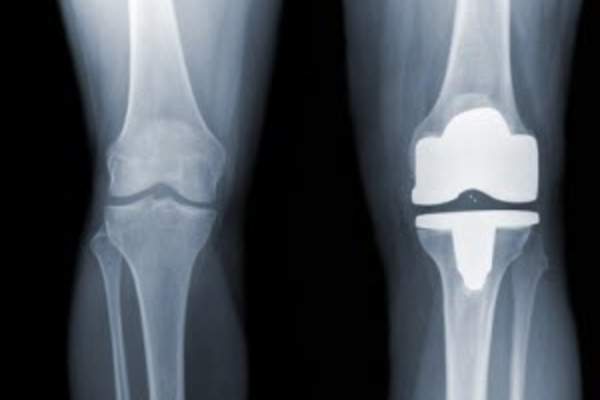

关于你的关节你不知道的7件事

人类的关节是惊人的结构,但它们也很容易受到损伤、发炎和磨损。了解更多关于你的关节以及如何保护它们免受关节炎的伤害。